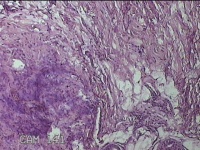

左侧会阴部皮下结节

性别

女

年龄

45岁

临床诊断

皮下结节

一般病史

发现左侧会阴部皮下结节2年余,伴近日局部隐痛不适。

标本名称

大体所见

灰白暗红色结节0.8x0.7x0.3cm一个,表面糜烂。

图3